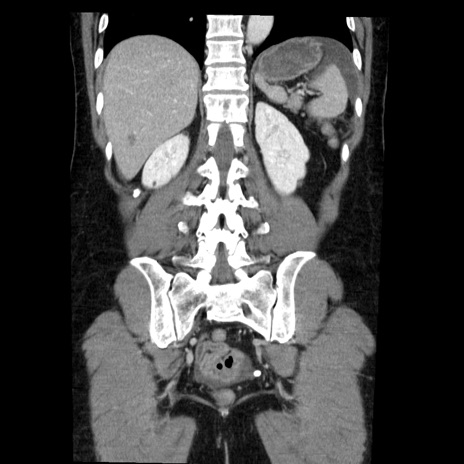

症例6(冠状断像)

【症例】50歳代女性

【主訴】下腹部痛

【現病歴】本日朝より下痢2回あり。 昼食を食べた後、嘔吐3回、下腹部痛認め、症状軽快せず、当院救急搬送。

最終食事:本日昼(生ものなし)。 昨日の夜、刺身を食ぺたとのこと。周囲に同様の症状の者なし。普段、排便は毎日あるとのこと。

【既往歴】卵巣癌術後(8年前に当院で卵巣摘出)

【身体所見】 意識清明、腹部:平坦、腸蠕動音→、やや硬、下腹部自発痛・圧痛あり、反跳痛あり、筋性防御なし。

【データ】WBC 16000、CRP 0.01